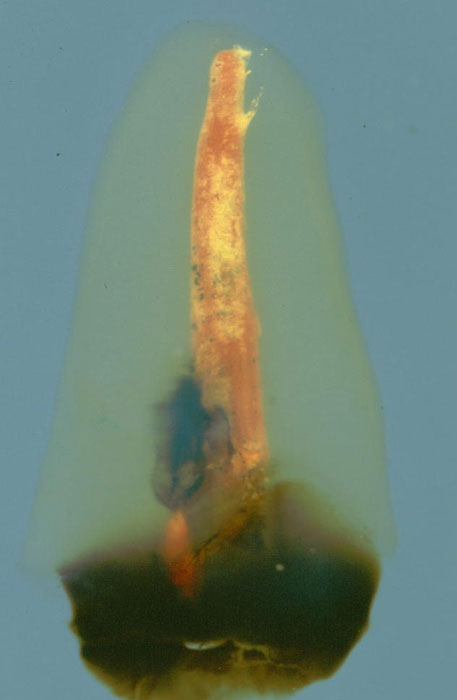

Zweiter unterer Prämolar als transparentes Präparat in der Ansicht von approximal

Fülltechnik: Apikaler Mastercone und Guttaperchakompaktierung mit einem

Kompaktor

Dicht erscheinende Füllung im Bereich der Wurzelkanalpräparation und der

finartigen akzessorischen Hohlräume

Im apikalen Drittel sind ein größerer und ein kleiner Seitenkanal aufgrund

von eingeflossenem Füllmaterial sichtbar.

Ein dichter Verschluss liegt in den Seitenkanälen nicht vor.

Die dunklen Pigmente im apikalen und mittleren Wurzeldrittel können nicht

zugeordnet werden.

ERGÄNZUNG: Ähnlicher Fall eines oberen zweiten Prämolaren als transparentes Präparat in der Ansicht von approximal

Die Wurzekanalfüllung füllt die Pulpahohlräume auf ganzer Länge gut aus

und erfasst den gesamten Querschnitt. D. Ricuccis histologische

Untersuchungen vergleichbarer Fälle deuten auf eine gute mikrobiologische

Abdichtung durch vollständige Wurzelkanalfüllungen hin.

Ein kleiner Seitenkanal ist durch eingeflossenen Sealer erkennbar.

Verteilung von Sealer und Guttapercha ist gut erkennbar.